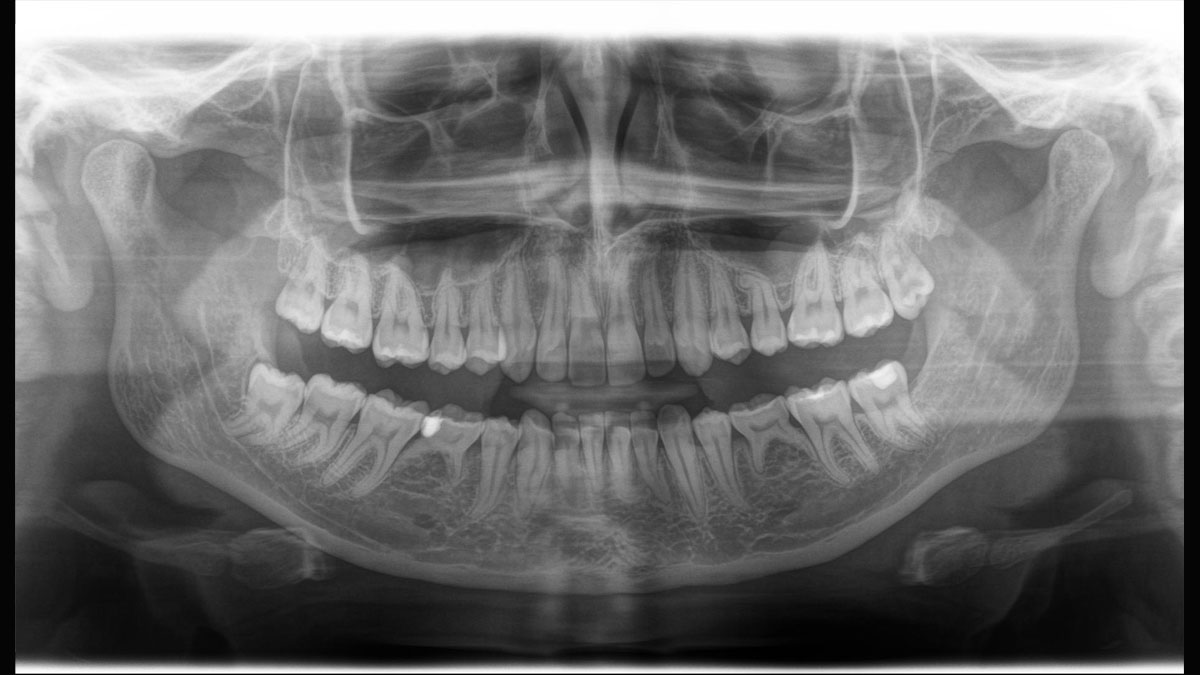

Der 2D/3D Power Performer Orthophos SL ist eine großartige Wahl für alle, die einfach mehr wollen. Der integrierte Direct Conversion Sensor (DCS) wurde für anspruchsvolle Bildqualitätsstandards entwickelt und bietet detaillierte Daten. Der intelligente Autofokus liefert automatisch fokussierte Panoramabilder mit hervorragender Gesamtschärfe. Orthophos SL bietet höchsten Bedienkomfort durch automatische Positionierung, eine anwenderfreundliche, intuitive Bedienung mit dem EasyPad und ein individuell einstellbares Umgebungslicht für ein exklusives Erscheinungsbild.

Der Direct Conversion Sensor erfüllt besonders hohe Standards für die 2D-Bildgebung

Der Autofokus erzeugt aus mehreren tausend Einzelbildern automatisch eine beeindruckende scharfe Panorama-Röntgenaufnahme

Der Direct Conversion Sensor (DCS) hat den Standard der Panorama-Bildgebung neu definiert. Röntgenstrahlen werden direkt in elektrische Signale umgewandelt – im Gegensatz zu herkömmlichen Systemen gibt es keinen Signalverlust durch Lichtumwandlung, was eine verbesserte Bildgebung ermöglicht. Das Ergebnis sind Bilder mit einer sehr hohen Schärfe, selbst bei niedriger Dosis.

Eine Röntgenaufnahme muss sofort diagnostizierbar sein. Der Autofokus hilft dabei erheblich. Orthophos SL erfasst mehrere tausend Einzelbilder in einem Zyklus und erkennt automatisch scharfe Bereiche, um ein gleichmäßig scharfes Gesamtbild zu erzeugen. Der intelligente Autofokus erfordert keine manuellen Arbeitsschritte vor und nach der Erfassung.